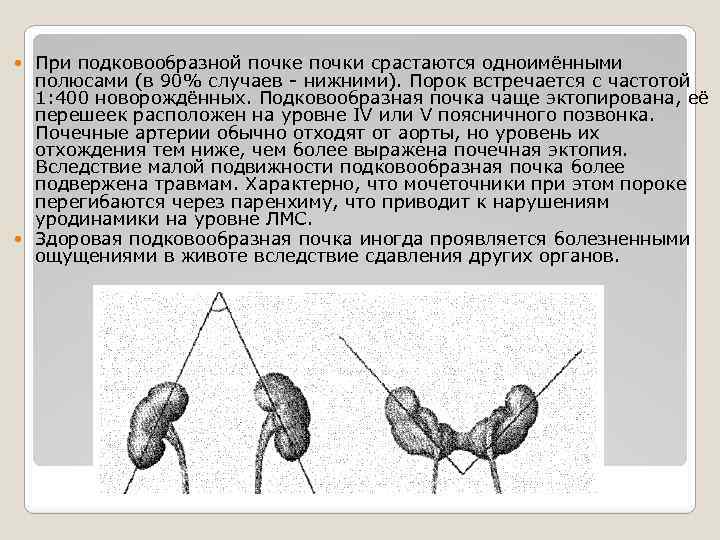

При подковообразной почке почки срастаются одноимёнными полюсами (в 90% случаев - нижними). Порок встречается с частотой 1: 400 новорождённых. Подковообразная почка чаще эктопирована, её перешеек расположен на уровне IV или V поясничного позвонка. Почечные артерии обычно отходят от аорты, но уровень их отхождения тем ниже, чем более выражена почечная эктопия. Вследствие малой подвижности подковообразная почка более подвержена травмам. Характерно, что мочеточники при этом пороке перегибаются через паренхиму, что приводит к нарушениям уродинамики на уровне ЛМС. Здоровая подковообразная почка иногда проявляется болезненными ощущениями в животе вследствие сдавления других органов.

При подковообразной почке почки срастаются одноимёнными полюсами (в 90% случаев - нижними). Порок встречается с частотой 1: 400 новорождённых. Подковообразная почка чаще эктопирована, её перешеек расположен на уровне IV или V поясничного позвонка. Почечные артерии обычно отходят от аорты, но уровень их отхождения тем ниже, чем более выражена почечная эктопия. Вследствие малой подвижности подковообразная почка более подвержена травмам. Характерно, что мочеточники при этом пороке перегибаются через паренхиму, что приводит к нарушениям уродинамики на уровне ЛМС. Здоровая подковообразная почка иногда проявляется болезненными ощущениями в животе вследствие сдавления других органов.